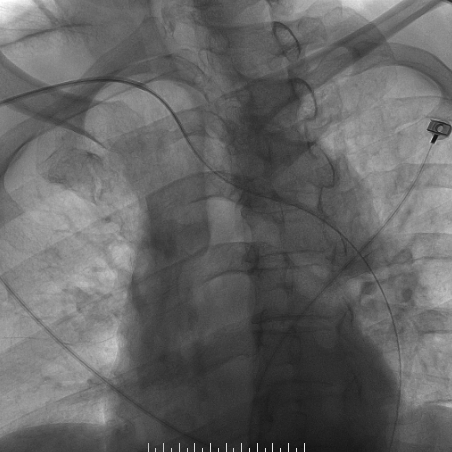

心脑联合造影

波科支架怎么样​径技·第165期|7F经桡入路下的颈动脉狭窄支架成形术一例_https://www.jmylbn.com_新闻资讯_第8张

波科支架怎么样​径技·第165期|7F经桡入路下的颈动脉狭窄支架成形术一例_https://www.jmylbn.com_新闻资讯_第9张

波科支架怎么样​径技·第165期|7F经桡入路下的颈动脉狭窄支架成形术一例_https://www.jmylbn.com_新闻资讯_第10张

-- 右侧颈内起始部中度狭窄,经前交通向左侧代偿

波科支架怎么样​径技·第165期|7F经桡入路下的颈动脉狭窄支架成形术一例_https://www.jmylbn.com_新闻资讯_第18张

波科支架怎么样​径技·第165期|7F经桡入路下的颈动脉狭窄支架成形术一例_https://www.jmylbn.com_新闻资讯_第19张

波科支架怎么样​径技·第165期|7F经桡入路下的颈动脉狭窄支架成形术一例_https://www.jmylbn.com_新闻资讯_第20张

-- 冠脉多发狭窄